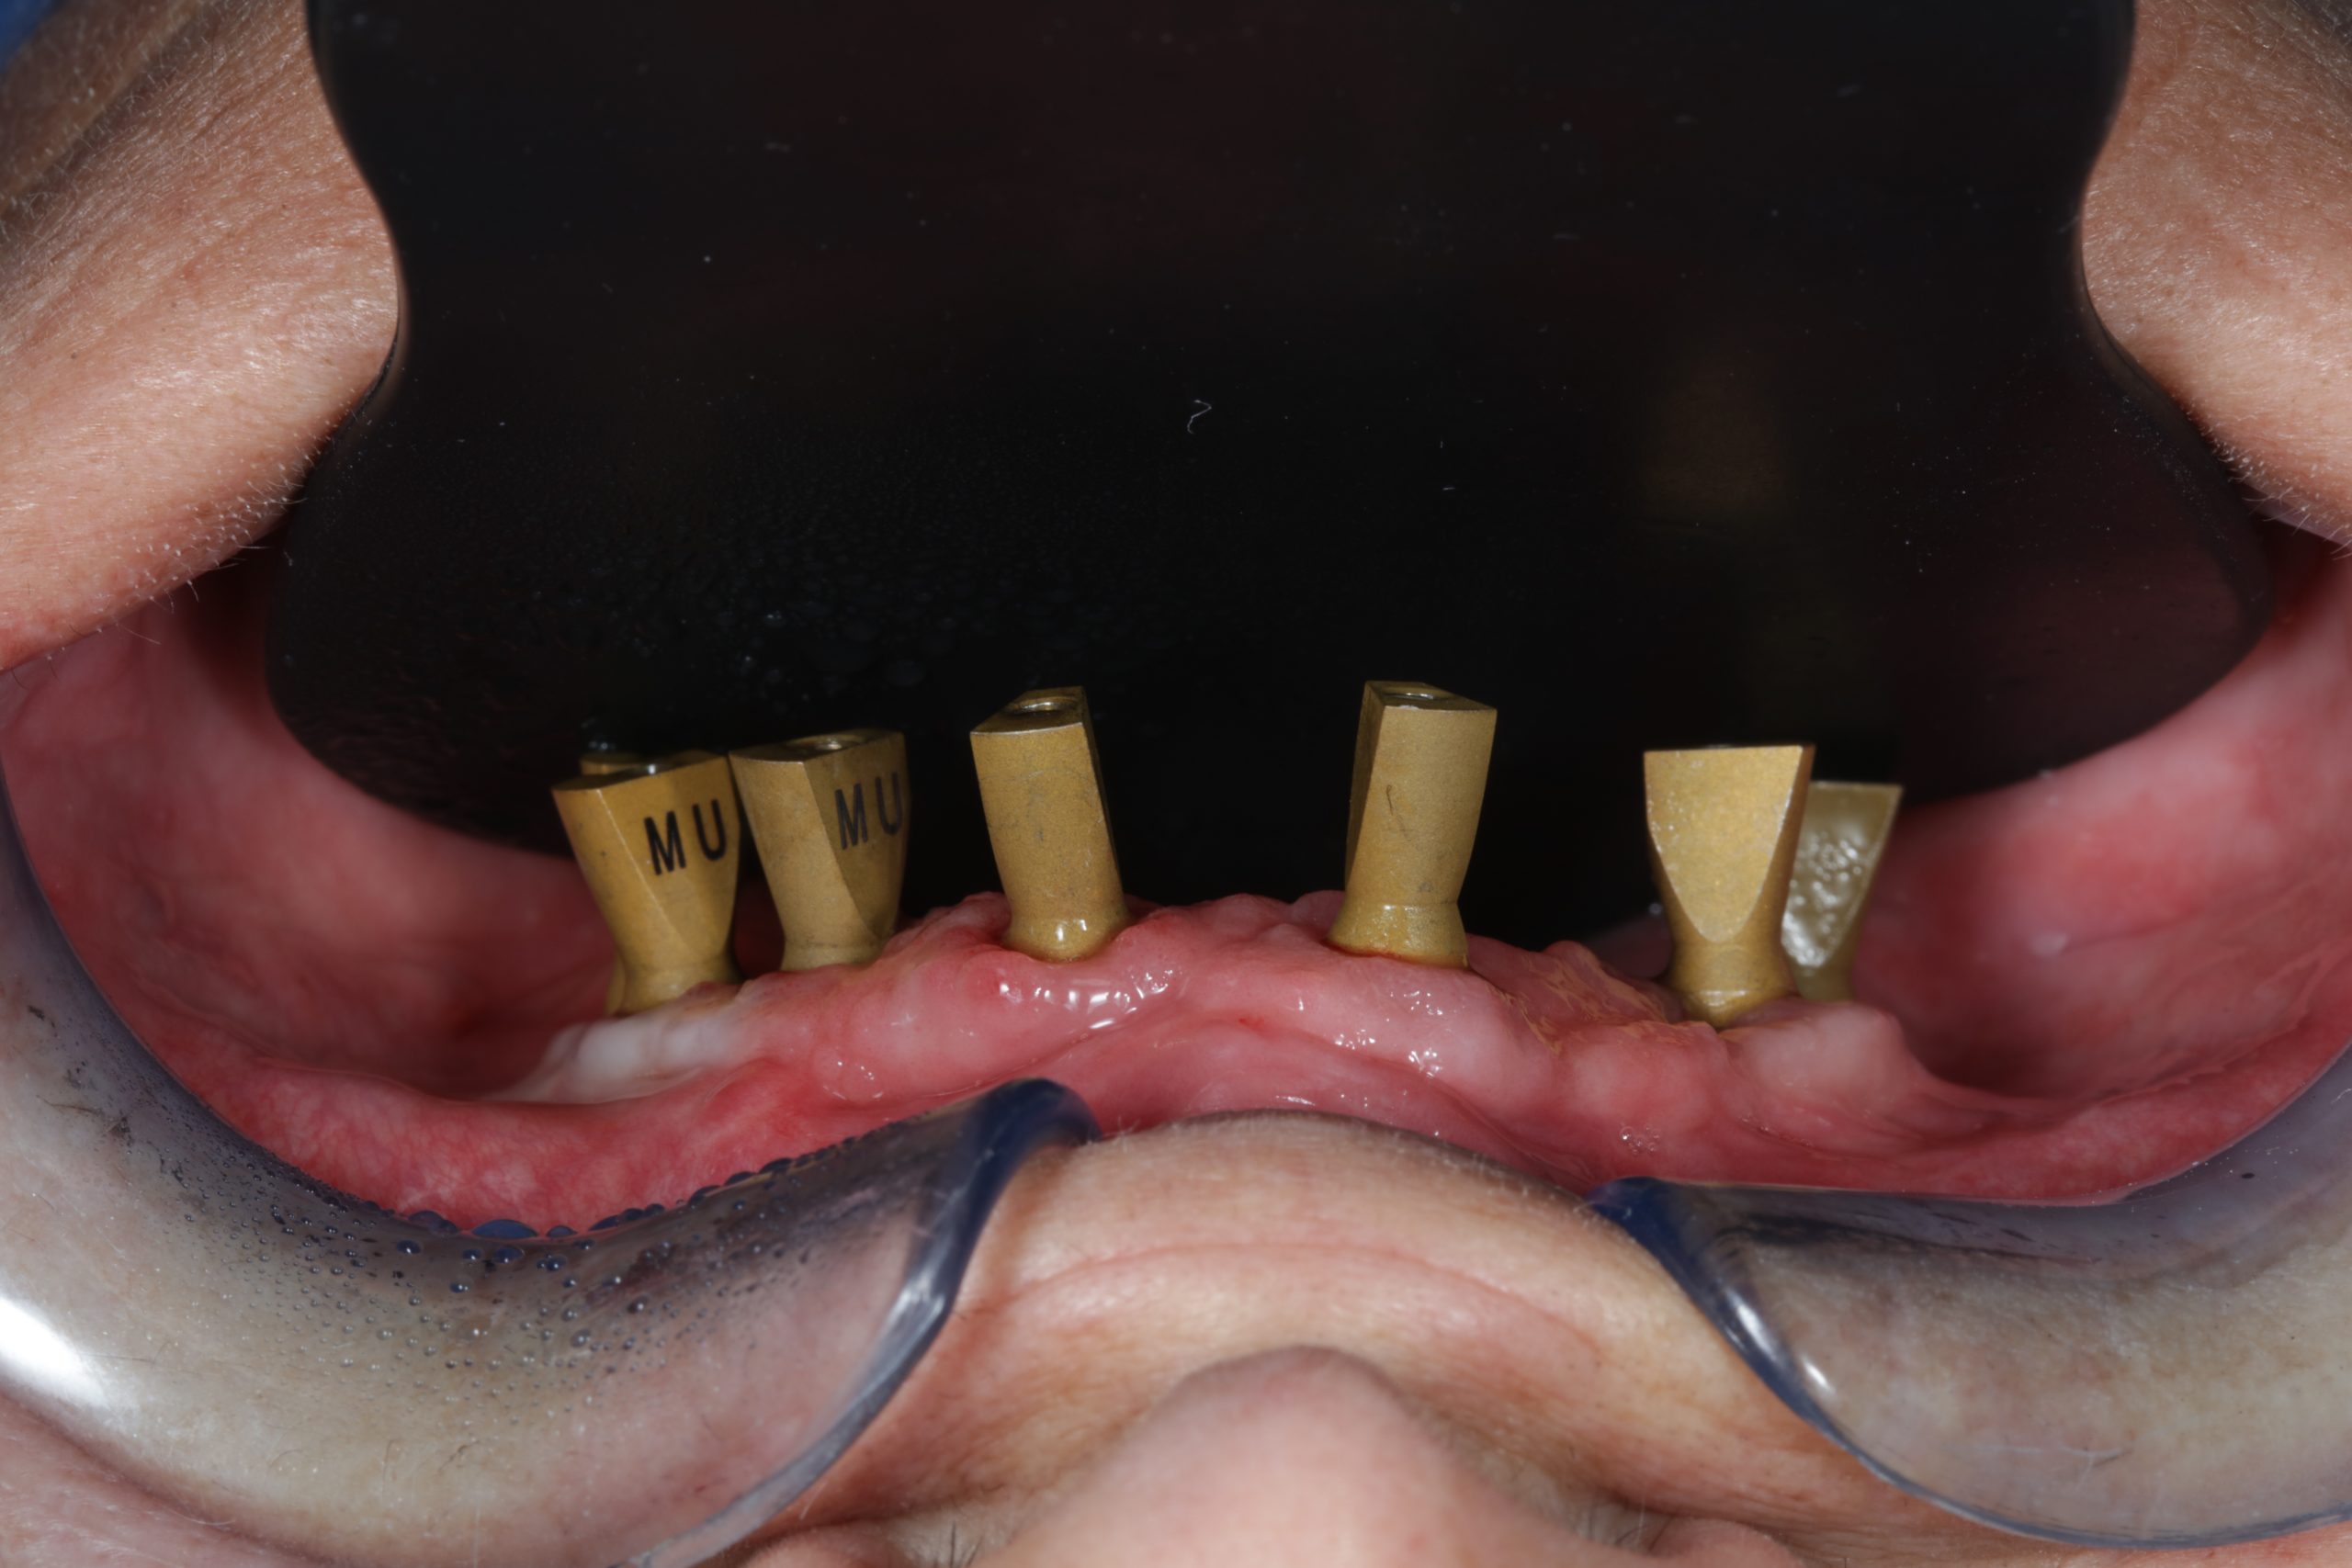

The use of CDP (Complete Digital Patient) as a basis for planning in a case of complete implant rehabilitation with a full arch in zirconia – ceramicised

Case study carried out with Athena Smile Pelekanos (GR ) : dott . Stavros Pelekanos